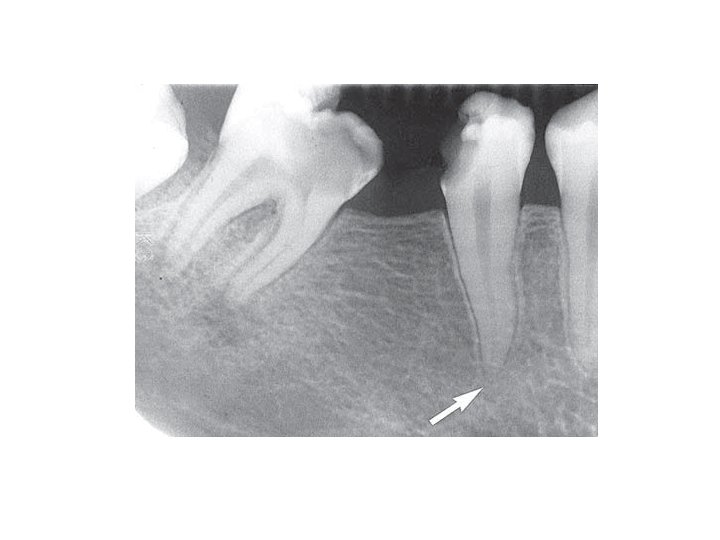

Peridontitis periapicalis chronica • Chronische Wurzelhautentzündung • Symptome: Es gibt sehr oft keine Symptome. • Röntgen: Periapikale Aufhellung-(Grenze ist nicht so scharf) Parodontalspaltverbreiterung

Abcessus periapicalis chronicus • abgekapselte Ansammlung von Eiter • Symptome: spontaner Zahnschmerz, Perkussionsschmerz Fistula, Gaumenschwellung Eiterbeule an der Gaumen • Röntgen: Irregulare und unscharfe Grenze, Aufhellung, (Granuloma ist dunkler)

Granuloma periapicale • abgekapselte Ansammlung von Granulationsgewebe • Symptome: Keine Schmerzen, Devitalität des betroffenen Zahnes. • Röntgen: rundliche Form, scharfe Grenze, periapikale Aufhellung • Histologie: Cyst > 1 cm (Fluidum) Granuloma < 1 cm (Granulationsgewebe)

Parodontitis lateralis chronica • Es gibt Seitekanale nach mesiale oder nach distale Richtung. Die Veränderung erscheint neben der Wurzel. • Symptome: Keine Schmerzen, Devitalität des betroffenen Zahnes. • Röntgen: rundliche Aufhellung im lateralen Parodontium.